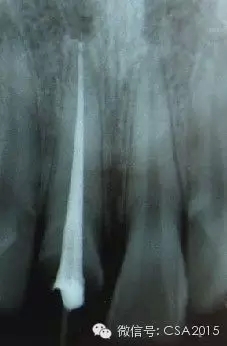

7 根管充填

封閉整個(gè)根管系統(tǒng)、堵塞主根管和側(cè)副根管出口、防止微生物和液體的滲漏。無(wú)論是側(cè)方加壓法還是垂直加壓法,應(yīng)做到根管充填致密,根管充填后X線片上無(wú)根管腔隙,也不能超出根尖孔。